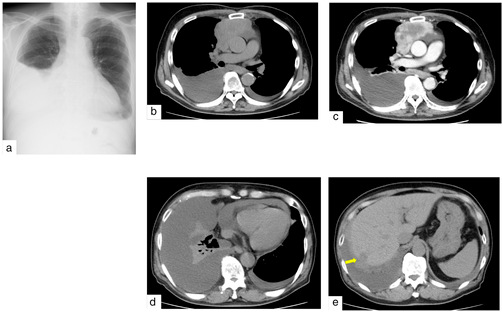

胸片显示右侧占优势的双侧胸腔积液(图1a)。计算机断层扫描(CT)显示前纵隔一个长轴为8cm的部分增强肿瘤(图1b,c),以及双侧胸腔积液、心包液(图1d)和多个肝脏结节(图1e)。右侧胸腔积液细胞学检查显示为V类恶性肿瘤,提示为小细胞癌。该肿瘤被认为是无法手术的原发性胸腺肿瘤,遂进行了CT引导下的肿瘤活检。

图1. 入院时成像。(a)胸部X线片显示右显性胸腔积液。(b,c)胸部计算机断层扫描(CT)显示前纵隔有一个8厘米的肿块,通过增强CT可部分增强。(d,e)CT显示双侧胸腔积液、心包液和肝结节(箭头)。